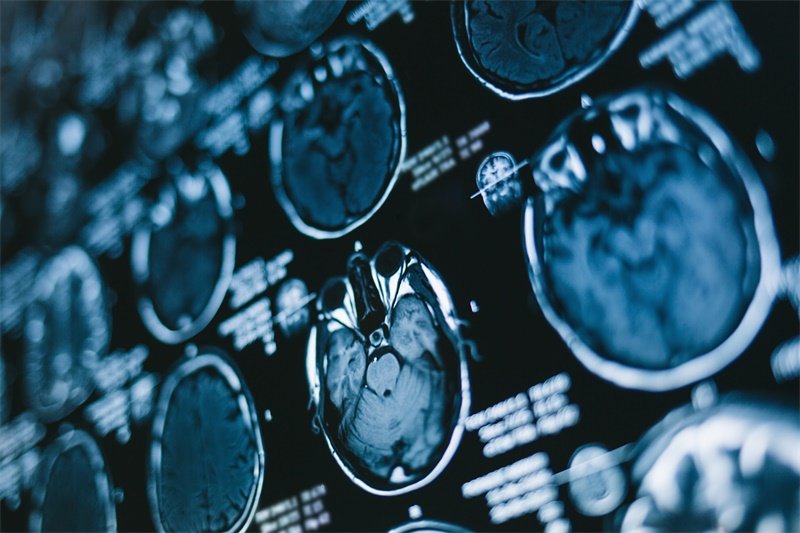

对脑环池占位性病变的诊断通常需要结合多种影像学检查,如CT和MRI。

2. MRI检查

MRI具有更高的分辨率,可以更加清晰地显示脑部占位性病变的细节。通过不同的扫描序列,医生可以进一步了解病变的性质,包括其形态、大小及对周围脑组织的影响。